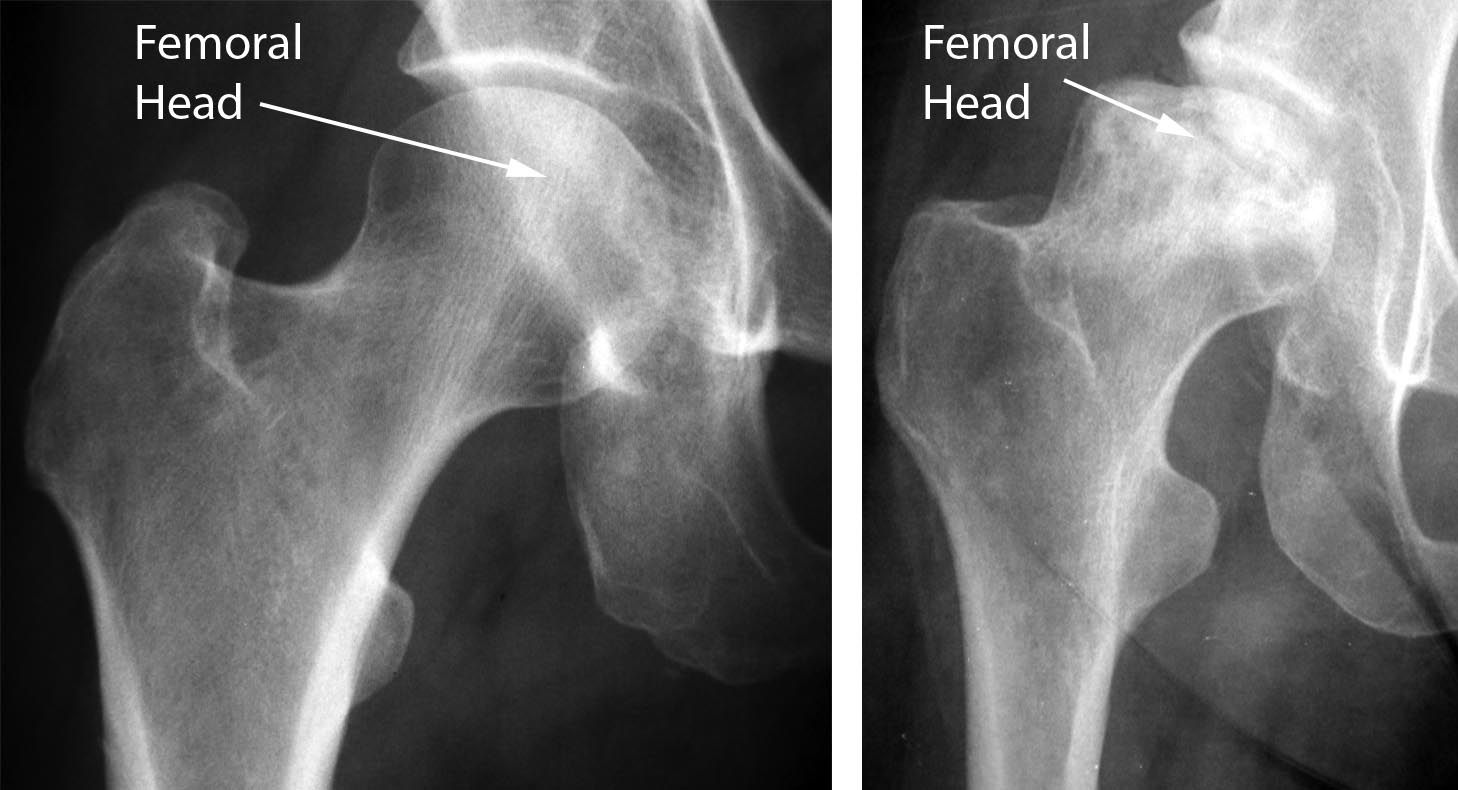

Osteonecrosis of the Hip OrthoInfo AAOS

Osteonecrosis of the Hip OrthoInfo AAOS What Would A Hip X Ray Show Most mri exams for hip pain take about 45 minutes. Begin by confirming the patient’s details , reviewing the clinical history and checking the radiographs are of the correct anatomical site (e.g. Patients with suspected inflammatory hip arthritis should be seen by a rheumatologist. This is a physician that specializes in patients with autoimmune diseases. What Would A Hip X Ray Show.